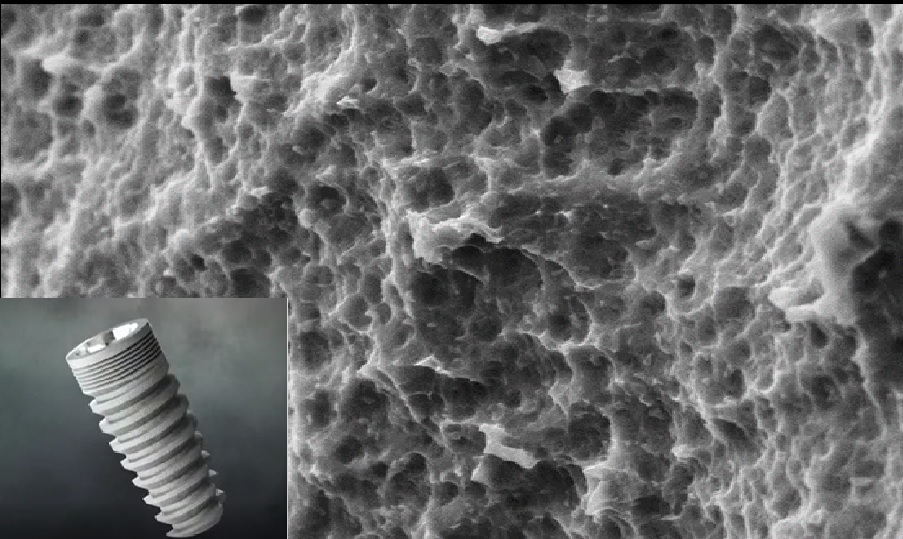

Figuring the need for an affordable implant system, Council of Scientific and Industrial Research (C.S.I.R) under the aegis of New Millennium India Technology Leadership Initiative (NMITLI) initiated a project on development of dental implants, which was led into its Phase I and II trials, under the entrustment of Prof. (Dr.) Mahesh Verma, Maulana Azad Institute of Dental Sciences and Prof. Naresh Bhatnagar, Indian Institute of Technology, Delhi. During this phase, dental implants were exquisitely designed and developed. Their safety and credibility was established through finite element analysis, mechanical testing, bio-compatibility, in - vivo implantation studies and Clinical trials, thus ensuring the highest standards of quality.

The osseointegration ofendosseous implant usually requires 3-6 months. Moreover, osseointegration in challenging situations, such as in immediate implant placement and immediate loading conditions is less predictable and requires bone formation at a faster rate. Considering the current status of global research, it is imperative to obtain indigenous solutions to address the mentioned concerns. For these situations there is a requirement of implants with a paradigm shift from friction closure to form closure and nanotopographic surfaces, which can achieve higher primary stability and fastest possible osseointegration to produce a predictable outcome. Hence, there is need for a next generation of implants, which can be placed in less ideal situations with reduced treatment time. Phase III of the project is concentrating on the enhancements in implant fixture structure, thread design, and surface micro-topography. It will help us develop the technology to address new-age clinical requirements.